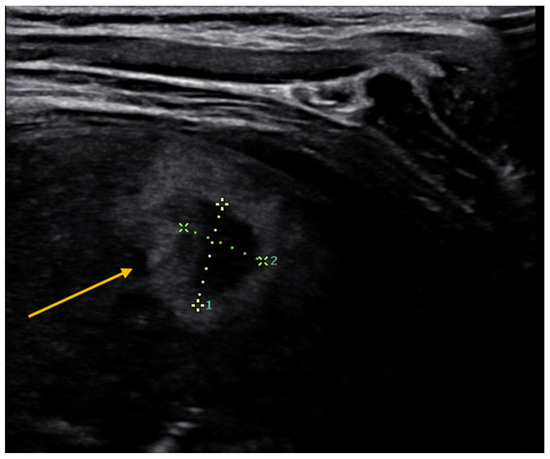

4.3. Lung Abscess

- Kraft, C.; Lasure, B.; Sharon, M.; Patel, P.; Minardi, J. Pediatric Lung Abscess: Immediate Diagnosis by Point-of-Care Ultrasound. Pediatr. Emerg. Care 2018, 34, 447–449. [Google Scholar] [CrossRef] [PubMed]

- Saoud, M.; Patil, M.; Singh Dhillon, S.; Alraiyes, A.H.; Sunar, U.; Harris, K. Image Characteristics of Lung Abscess by Convex-Probe Endobronchial Ultrasound. J. Bronchol. Interv. Pulmonol. 2017, 24, 34–35. [Google Scholar] [CrossRef] [PubMed]